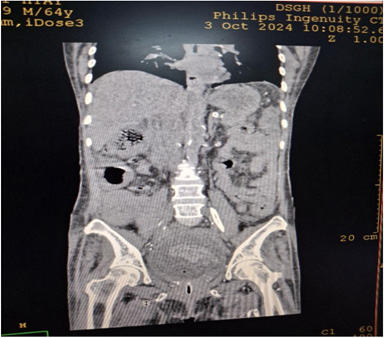

Cystoscopy was done to detect mucosa lesions in bladder; the whole mucosa was congested and red. There were multiple hemorrhagic areas in whole bladder mucosa; it was bled on touch. There was no focal ulcer or tumor. Therefore, generalized congested mucosa, hemorrhagic areas were probably due to DIC or CMV cystitis or candida cystitis or bacteria cystitis. The color of urine coming from Vescio-ureteric orifice of graft kidney was clear. Hemostasis was done with Ball electrode; bladder wash out was done with Tomey’s glass syringe. Figure 9-15 reveal cystoscopy findings. Abdominal tomogram was done; it revealed a swollen allograft kidney with air in the renal pelvis and renal vessels and subcapsular area suggestive of emphysematous allograft pyelonephritis. And, air along bladder wall was seen indicating emphysematous cystitis. They are illustrated in (Figure 16-19).

Figure 16: CT abdomen axial view non-contrast showing swollen allograft kidney with air in the renal pelvic.

Figure 17: CT abdomen coronal view non-contrast showing swollen allograft kidney with air in the renal pelvic, subcapsular area and air along bladder wall.

Figure 18: CT abdomen coronal view non-contrast showing swollen allograft kidney with air in the renal pelvic, subcapsular area and air in the bladder.